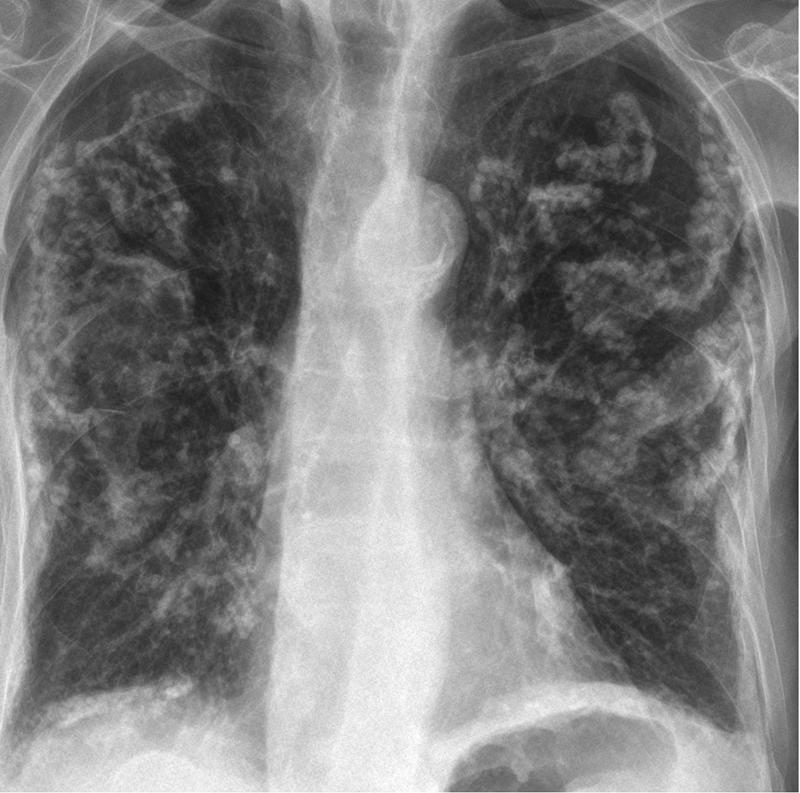

Asbestos- calcified plaques